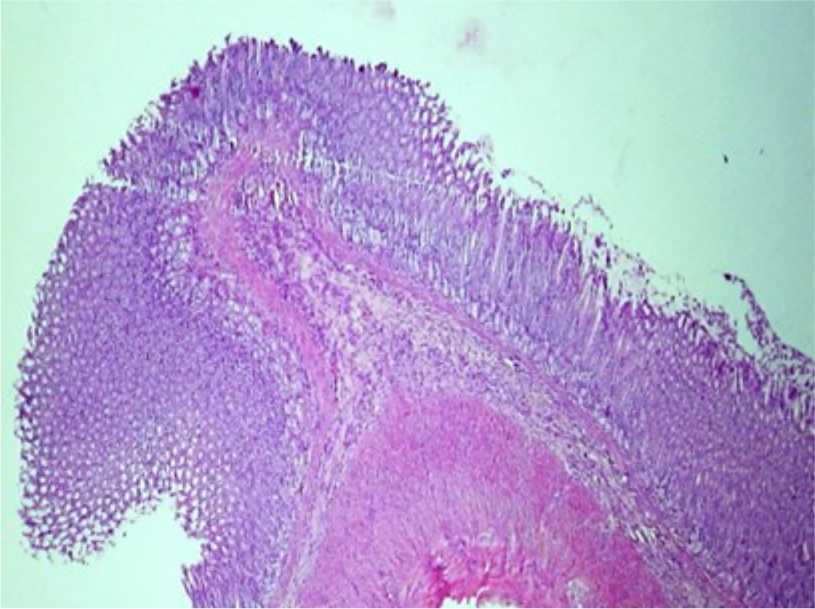

При проведении патоморфологического исследования у животных из второй группы на 3-й день было выявлено, что поверхностный железистый эпителий слизистой оболочки в состоянии атрофии, тотально слущивается (Рис.5). Эпителий, выстилающий железы представлен в основном слизистыми экзокриноцитами, что придает железам пенистый вид, просветы желез расширены. Очагово отмечается атрофия и слущивание эпителия, также присутствуют фокусы гомогенизации желез – отек. Васкуляризация стенки желудка активная. Сосуды гиперемированы, в слизистой оболочке в собственно-слизистом слое отмечается стаз крови в капиллярах.

Рис. 5. Атрофия и слущивание поверхностного эпителия. Ув. ×200

У второй группы животных на 3-й день обнаружена атрофия и слущивание эпителия, присутствуют фокусы гомогенизации, но некробиоза экзокриноцитов не выявлено.